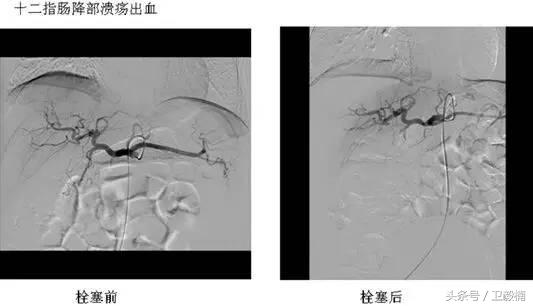

2、经导管血管栓塞法(Transcatheter embolization)

经原血管造影的导管或特制的导管,将栓塞物送至靶血管内,一是治疗内出血如外伤性脏器出血、溃疡病、肿瘤或原因未明的脏器出血。另一是用栓塞法治疗肿瘤,因肿瘤循环部分或全部被栓塞物阻断,以达控制肿瘤之生长,或作为手术切除的一种治疗手段;亦可用于非手术脏器切除,例如注射栓塞物质于脾动脉分支内,即部分性脾栓塞,以治疗脾功亢进,同时不影响脾脏的免疫功能。

常用的栓塞物质如自体血凝块、明胶海绵、无水酒精、聚乙烯醇、液体硅酮、不锈钢圈、金属或塑料小球及中药白芨等。